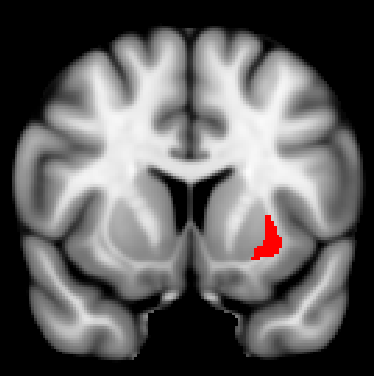

Habenula anatomy and function… Image The habenula is a tiny, pea-sized structure that sits atop the pineal gland.

On coronal images you can find it bulging into the 3rd ventricle right above the posterior commissure. Image